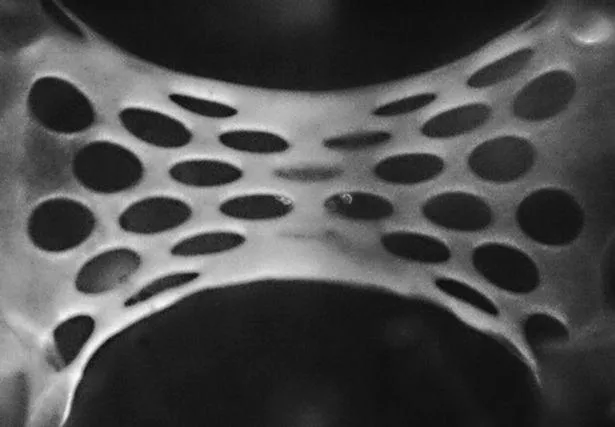

Пластырь содержит до 50 миллионов человеческих стволовых клеток, которые превращаются в здоровую сердечную мышцу. Разработка содержит вещества, которые способны восстанавливать и обновлять клетки сердца.

Пластырь содержит до 50 миллионов человеческих стволовых клеток

По словам исследователей, пластыри подпитывались кровеносными сосудами, которые растут от сердца реципиента.